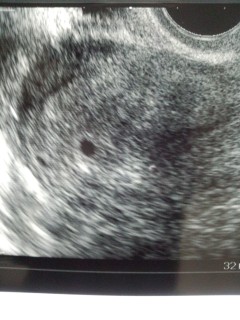

ちゃんと着床してたよーっ!小さな点が、赤ちゃんに栄養を与えている袋だよ!と…言われました。 着床出血があり、えーーっ!と、ビックリしましたが、無事だったようです。その後、出血もなく…あと、2週間後が楽しみすぎるー! 早く心拍確認したいです! いまのところ、つわりはない感じですが…胸焼けが少しある気がする…